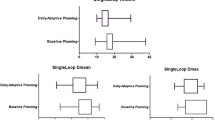

For each margin selected, the relative volume of the mesorectum differed significantly from the relative volume of the mesorectum of the other margins (p < 0.001). The graph shows that an increase in the selected margin was accompanied by an increase in relative volume (Fig. 3).

Boxplot shows the relationship between the upper mesorectum volume on CBCT relative to the planning CT scan with selected margin. It shows the interquartile range, with a horizontal line showing the group median. Whiskers indicate the 5th and 95th percentiles. Outliers are marked. One-way ANOVA testing with Bonferroni correction applied showed all margins to be significantly different (p < 0.001)